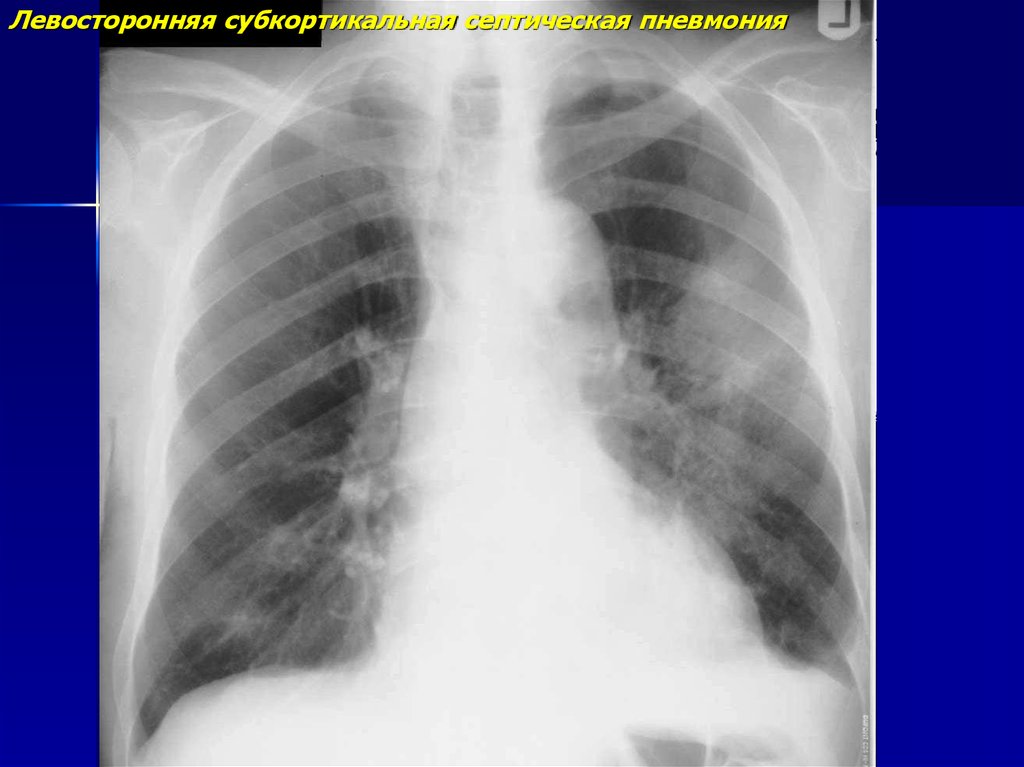

18.

Левосторонняя субкортикальная септическая пневмония